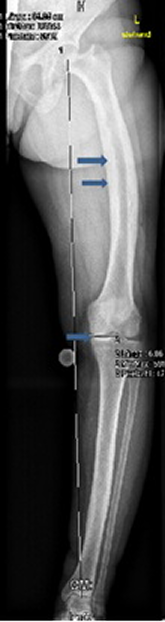

Sagittal T1-weighted MRI of the left knee showed no attachment of the posterior horn of the medial meniscus to the tibial plateau, but instead the meniscofemoral ligament (ligament of Wrisberg) joined the posterior horn of the meniscus to the lateral surface of the medial femoral condyle, i.e. discontinuity between the anterior and posterior horns, causing effectively the development of degenerative lesion of the posterior horn of the left medial meniscus (Figure 1 [Fig. 1]). On the bases of skeletal survey, weight bearing anteroposterior left lower limb radiograph showed varus deformity of the left lower extremity and narrowing of the medial knee joint and narrowing of the hip joint as well associated with unusual cortical thickening and bone enlargement. The angles of the frontal plane alignment were measured according to Paley: mechanical lateral distal femoral angle (mLDFA) = 106°, medial proximal tibial angle (mMPTA) = 85°, and the distal tibial angle (mLDTA) = 93°. These measurements were compared to weight bearing full length radiographs, which are considered to be the standard of reference for planning corrective surgery. The lateral distal left femoral angle measured 106°, which means approximately 20° deviation from the norms (Figure 2 [Fig. 2]). Skull radiographs showed the cotton wool appearance, disorganized trabecular with areas of sclerosis which are poorly defined and fluffy. Widening of the diploic space and relatively indistinct outer table, and the frontal sinuses are enlarged. No hyperostosis of the skull base was noted. These findings reflect the underlying pathologic changes of osteoblastic repair and are usually pathognomonic (Figure 3 [Fig. 3]). The patient underwent laboratory investigations with blood and urinary tests. Serum bone alkaline phosphatase was high (four times greater than the normal value), which is reflective of the rapid new bone turnover. Other laboratory studies showed normal levels of calcium, phosphate, PTH and vitamin D levels.

Figure 2: Weight bearing anteroposterior left lower limb radiograph shows varus deformity of the left lower extremity and narrowing of the medial knee joint and narrowing of the hip joint as well associated with unusual cortical thickening and bone enlargement (arrows). The lateral distal left femoral angle measured 106 °, which means approximately 20° deviation from the norms (arrow).